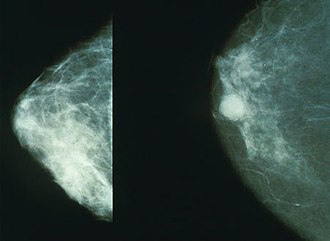

Mamografija

Mamografija je točna i sigurna rendgenološka pretraga (danas se koristi samo pedeseti dio doze zračenja potrebne u početku) kojom se otkrivaju tumori i druge promjene, premalene da bi se mogle napipati. Mamografski pregled u većini slučajeva nije bolan. U mladih žena žljezdano tkivo zauzima gotovo cijelu dojku i mamografska slika je prilično nejasna, stoga je uobičajeno da nema razloga (osim iznimno) snimati dojke žena mlađih od 35 godina. Prvu mamografiju tzv. bazični (inicijalni) mamogram savjetuje se napraviti ženama između 38. i 40. godine, a zatim ženama starijim od 40 godina jednom godišnje. U žena u dobi od 50-69 godina preporuka je mamografiju napraviti minimalno jednom u dvije godine. Mamografija obuhvaća dvije snimke dojke uz maksimalno stlačivanje dojki (pritiskom na dojku kompresijskom pločom), snimku dojke sprijeda te s njezine bočne strane, koje prikazuju njezinu građu i sumnjiva mjesta. Unatoč nezamjenjivosti mamografije u ranom otkrivanju i najmanjih karcinoma, važno je naglasiti da se mamografijom ne može prikazati 15-20 % karcinoma dojki, osobito kad se radi o dojkama s gustom žljezdanom strukturom. U Hrvatskoj se radi dogovora za mamografiju treba javiti svom izabranom liječniku obiteljske medicine ili ginekologu.